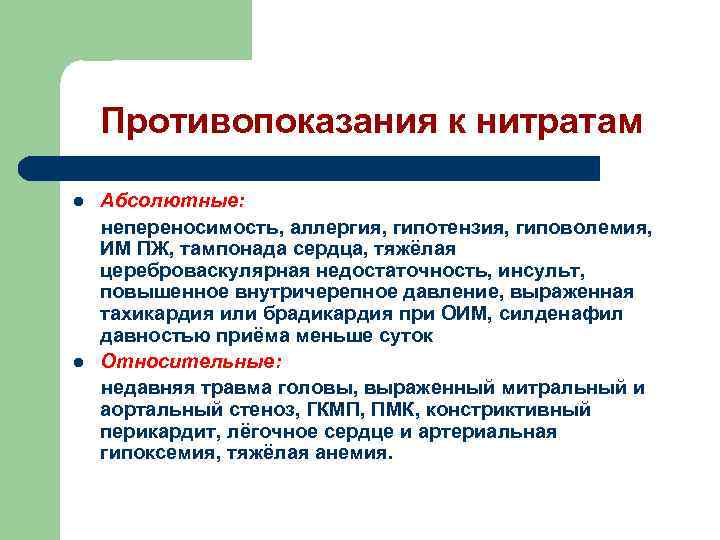

Противопоказания к нитратам l l Абсолютные: непереносимость, аллергия, гипотензия, гиповолемия, ИМ ПЖ, тампонада сердца, тяжёлая цереброваскулярная недостаточность, инсульт, повышенное внутричерепное давление, выраженная тахикардия или брадикардия при ОИМ, силденафил давностью приёма меньше суток Относительные: недавняя травма головы, выраженный митральный и аортальный стеноз, ГКМП, ПМК, констриктивный перикардит, лёгочное сердце и артериальная гипоксемия, тяжёлая анемия.